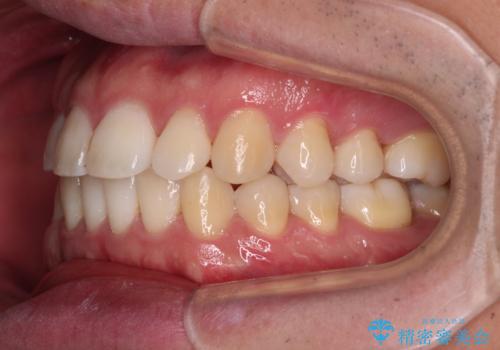

インビザラインで奥歯の咬み合わせと前歯のデコボコを改善

- 前歯のデコボコと奥歯の咬み合わせを気にして来院された患者様です。

前歯のデコボコはインビザラインで十分に対応可能と判断できましたが、咬合力が強いため、臼歯(特に右側)の交叉咬合はインビザライン単体では困難と思われました。

まずはインビザライン単体で矯正治療を開始し、交叉咬合が改善されない場合にはアンカースクリューなどの使用を検討することとしました。

インビザライン単体では右側の交叉咬合を解消することができなかったため、アンカースクリューを併用して咬合を改善させました。